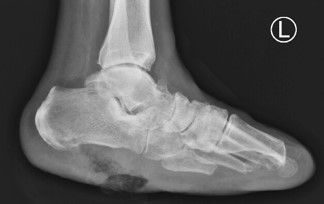

Left foot radiographs showed significant soft tissue defects and osteolysis within the inferior calcaneus, highly suspicious of underlying osteomyelitis (Figure 2). A Magnetic Resonance Imaging (MRI) of the left foot was ordered for further evaluation of underlying osteomyelitis. The result was concerning for osteomyelitis within the calcaneus with multiple punctate low signal foci suspicious of emphysematous osteomyelitis. The MRI also showed multiple fluid collections within the hindfoot and midfoot (Figure 3).

Figure 2: Non-weight bearing left plain radiographs with notable large plantar foot soft tissue ulcerations extending to the calcaneus with adjacent inferior calcaneus ill-defined ostial lytic lesions. Prior transmetatarsal amputation. Noted vascular calcifications.

Our case study provides a unique presentation of emphysematous osteomyelitis of the foot. To the author’s knowledge based on a thorough database search, one other article was identified with emphysematous osteomyelitis within the calcaneus, which concurrently presented with subcutaneous emphysema [7]. The patient in the Gruenberg case study, unfortunately, required above-knee amputation after serial debridement’s secondary to the extent of the infection [7]. Our patient had a dissimilar presentation of their calcaneal infection, as there was no surrounding subcutaneous emphysema (Figure 2) but did require a below-knee amputation. The difficulty with our patient was that the infection was not easily identifiable on plain radiographs, leading to a delay in diagnosis until advanced imaging was completed. There is no agreement in the current literature on the use of plain radiographs for accurate identification of emphysematous osteomyelitis. Once the diagnosis of emphysematous osteomyelitis was made, a multi-disciplinary team was assembled that included podiatry, vascular surgery, infectious diseases, and medicine team, allowing prompt, decisive decision-making and urgent intervention that saved the patient from a more proximal amputation or worse fate.